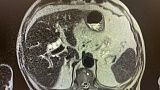

1)УЗИ органов брюшной полости: внутрипеченочные протоки расширены ,общий печеночный проток расширен, холедох до 12 мм, визуализируется фрагментарно. Заключение: Холедолитиаз. Билиарная гипертензия.

2)Биохимический анализ крови: Билирубин- 82,4 , прямой- 47,5 АЛТ- 92 , АСТ-136 , С-реактивный белок -44,4 скорость клубочковой фильтрации- 45 . МРТ: внутри- и внепеченочные протоки расширены , общий печеночный проток до 18 мм, холедох до 14 мм, в просвете конкременты до 14 мм. Заключение: Холедохолитиаз . Билиарная гипертензия.